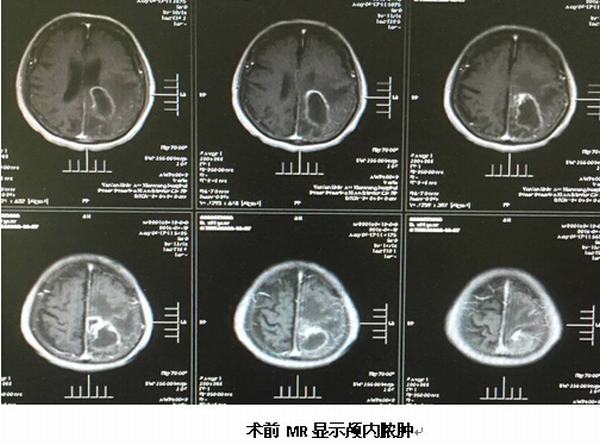

2016年4月21日凌晨2點,閆女士突然出現(xiàn)頭痛、左側(cè)肢體無力等癥狀,當(dāng)晚即被家人緊急送醫(yī),經(jīng)查,她大腦的右側(cè)顳葉出現(xiàn)腦出血。經(jīng)過細(xì)致的準(zhǔn)備,我院神經(jīng)外科醫(yī)護(hù)人員為閆女士實施了腦立體定向手術(shù),術(shù)前安裝頭架,頭顱CT掃描,設(shè)定靶點并計算坐標(biāo),術(shù)中安裝弓形架等,將引流管精確植入靶點---血腫正中心,順利抽出血腫,術(shù)后CT驗證立體定向手術(shù)精確。現(xiàn)經(jīng)治療10多天后患者已獨立下床活動,恢復(fù)理想。

繼完成第一例腦立體定向手術(shù)后不久,于2016年4月25日我院神經(jīng)外科又完成一例89歲高齡腦膿腫患者的腦立體定向膿腫穿刺引流術(shù),按照手術(shù)標(biāo)準(zhǔn)流程操作,術(shù)中清除膿液約30ml,經(jīng)置管持續(xù)引流并局部及全身注射抗菌素治療,目前患者頭顱CT顯示膿腔已消失,體溫正常,神志清楚,各項生命體征平穩(wěn)。